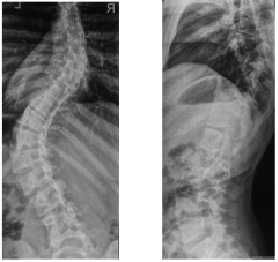

Ретроспективный анализ показал, что наибольшая величина коррекции наблюдалась у пациентов, которым применяли I вариант оперативного лечения. После хирургического вмешательства остаточная деформация сколиотической дуги деформации составила от 0 ° до 17 ° (средняя величина остаточной деформации - 7 °), процент коррекции колебался от 74 % до 100 % (средний процент коррекции - 86,6 %). Остаточный угол ротации апикального позвонка составил от 10 ° до 27 ° (средний остаточный угол ротации 18,5 °). Средний процент деротации апикального позвонка составил 24,4 % (рис. 2 А, Б). Такие результаты лечения объясняются наличием сколиотической деформации, не превышающей 85 °, мобильной сколиотической дугой искривления и применением в качестве опорных элементов спинальной системы с транспедикулярными опорными элементами. Тотальная транспедикулярная фиксация, используемая при коррекции сколиотической деформации, позволила осуществить равномерное распределение нагрузки вдоль опорных элементов металлоконструкции и предотвратить в дальнейшем потерю коррекции достигнутого результата в послеоперационном периоде наблюдения.

А

Б

Рис. 2. Рентгенограммы позвоночника пациентки К., 16 лет. Идиопатический левосторонний грудопоясничный сколиоз IV степени: А - до операции, угол деформации 70 ° по Cobb; Б - после операции, угол деформации 17 ° по Cobb